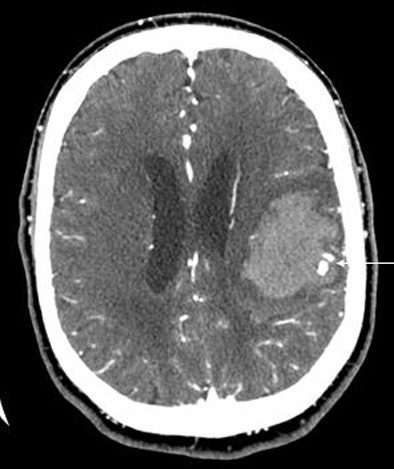

| A 64-year-old man presented with acute onset of right arm weakness and aphasia. The patient underwent CT/CTA. Neuroradiologists were initially concerned the CT findings (arrows, above and below) represented an AV malformation. Further examination left them unable to track the contrast through any vascular distribution, however, and they hypothesized that the findings represented contrast extravasation. Two hours later the patient suffered significant clinical deterioration; repeat head CT showed hematoma expansion. Direct angiography showed no AVM, and subsequent surgical excision found only hematoma and no vascular malformation. In 104 patients, lack of a spot sign had a 98% negative predictive value for identifying patients who would not have hematoma expansion at follow-up. Image courtesy of Dr. Joshua Goldstein. |